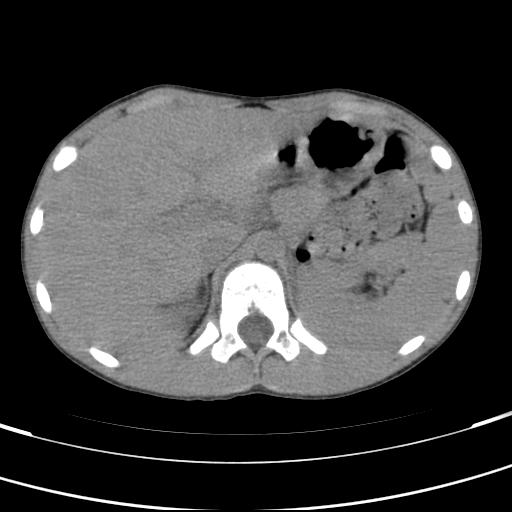

标题: PED3157:左肾缺如,请教脾脏的改变?、、

男孩,9岁。胃部不适。

脾脏位于左侧,但数个脾脏呈分离状态,左肾缺如,右肾代偿肥大。考虑多脾综合征。

脾脏变异,左肾未见,游走、异位、发育不全都要可能,增强或ivp造影。